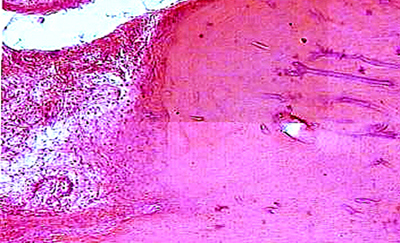

Важным условием для течения любого раневого процесса, в том числе и в костной ране, является завершенное течение фазы воспаления и создание условий для нормализации процессов энергопродукции и появления возможности для избыточного анаболизма. На временные критерии возникновения этого состояния значительное влияние оказывает состояние кровообращения в области повреждения и всем сегменте конечности в целом. Развивающаяся в результате травмы дезинтеграция кровоснабжения приводит к нарушению оксигенации тканей. Выраженность и протяженность области сосудистых нарушений, дестабилизации ультраструктур микроангиоархитектоники и особенно путей оттока крови находится в прямой зависимости от энергии травмирующего агента. Прогрессирование дистрофических процессов в тканях конечности после травмы в значительной мере зависит от посттравматических микроангиопатий, развивающихся на фоне нарушений в венозном отделе микроциркуляторного русла, что приводит к формированию трансэндотелиальных каналов и люков, плазматическому пропитыванию стенки сосудов, ее гиалинозу и склерозу. Вследствие этих изменений возникает нарушение транскапиллярного обмена, нарастает гипоксия и существенно ухудшается трофическое обеспечение тканей конечности. Наряду с этим, снижение объемного уровня кровотока в микроциркуляторном русле поврежденного участка приводит к нарушению информационных процессов между зоной повреждения и лимфоидными органами и, как следствие, замедлению или редукции течения воспалительного процесса. На длительность стадии разрушения и дедифференцировки клеток значительное влияние оказывает дисбаланс энергетических процессов. В результате гипоксии в поврежденных тканях нарушается соотношение циклических нуклеотидов (цАМФ и цГМФ), посредством которых реализуется воздействие нейрогуморальной регуляции биохимических процессов в клетке. Вследствие этого нарушаются регуляторные механизмы процессов энергопотребления в клетке – они не соответствуют скорости энергопродукции. Результатом энергетического дисбаланса является преобладание эрготропных процессов над трофотропными и превалирование процессов ассимиляции над диссимиляцией.